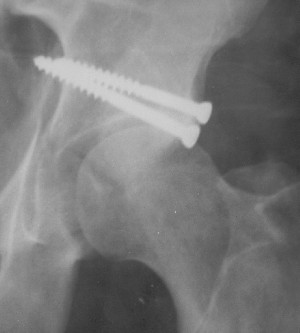

Уважаемые коллеги. Больной был оперирован в одну сессию 25 августа. Сначала на голень наложен спице-стержнвой аппарат. Затем выполнен остеосинтез вертлужной впадины Y-образным доступом. Пришлось дополнительно отсекать вертел. Шейка синтезирована спонгиозными винтами и спицами, вертел - спицами и стягивающей петлей. После операции находился на вытяжении 3 нед. Раны зажили первичным натяжением. Сейчас уже дома. Будет и дальше без нагрузки на левую ногу. Будем наблюдать в динамике. Ждем комментарии.

Привет Алекей! Сделано неплохо, поздравляю, хотя второй винтик можно было бы и подлиннее в шейку загнать! Пара вопроов: доступ такой же? головка была свободной или висела на капсуле?